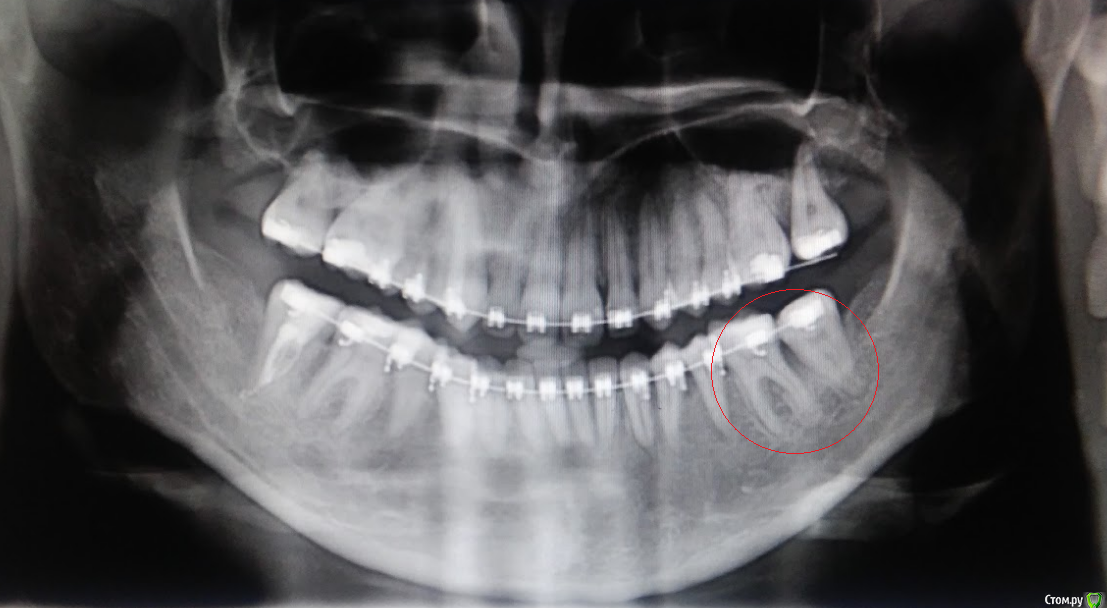

колесников Опубликовано 19 мая, 2017 Поделиться Опубликовано 19 мая, 2017 Мало данных. Приложите рентгеновский снимок этого участка. Ссылка на комментарий

catalystka Опубликовано 23 мая, 2017 Автор Поделиться Опубликовано 23 мая, 2017 Есть панорамный снимок. К сожалению, на пленке мне его не дали, есть только фото. Ссылка на комментарий